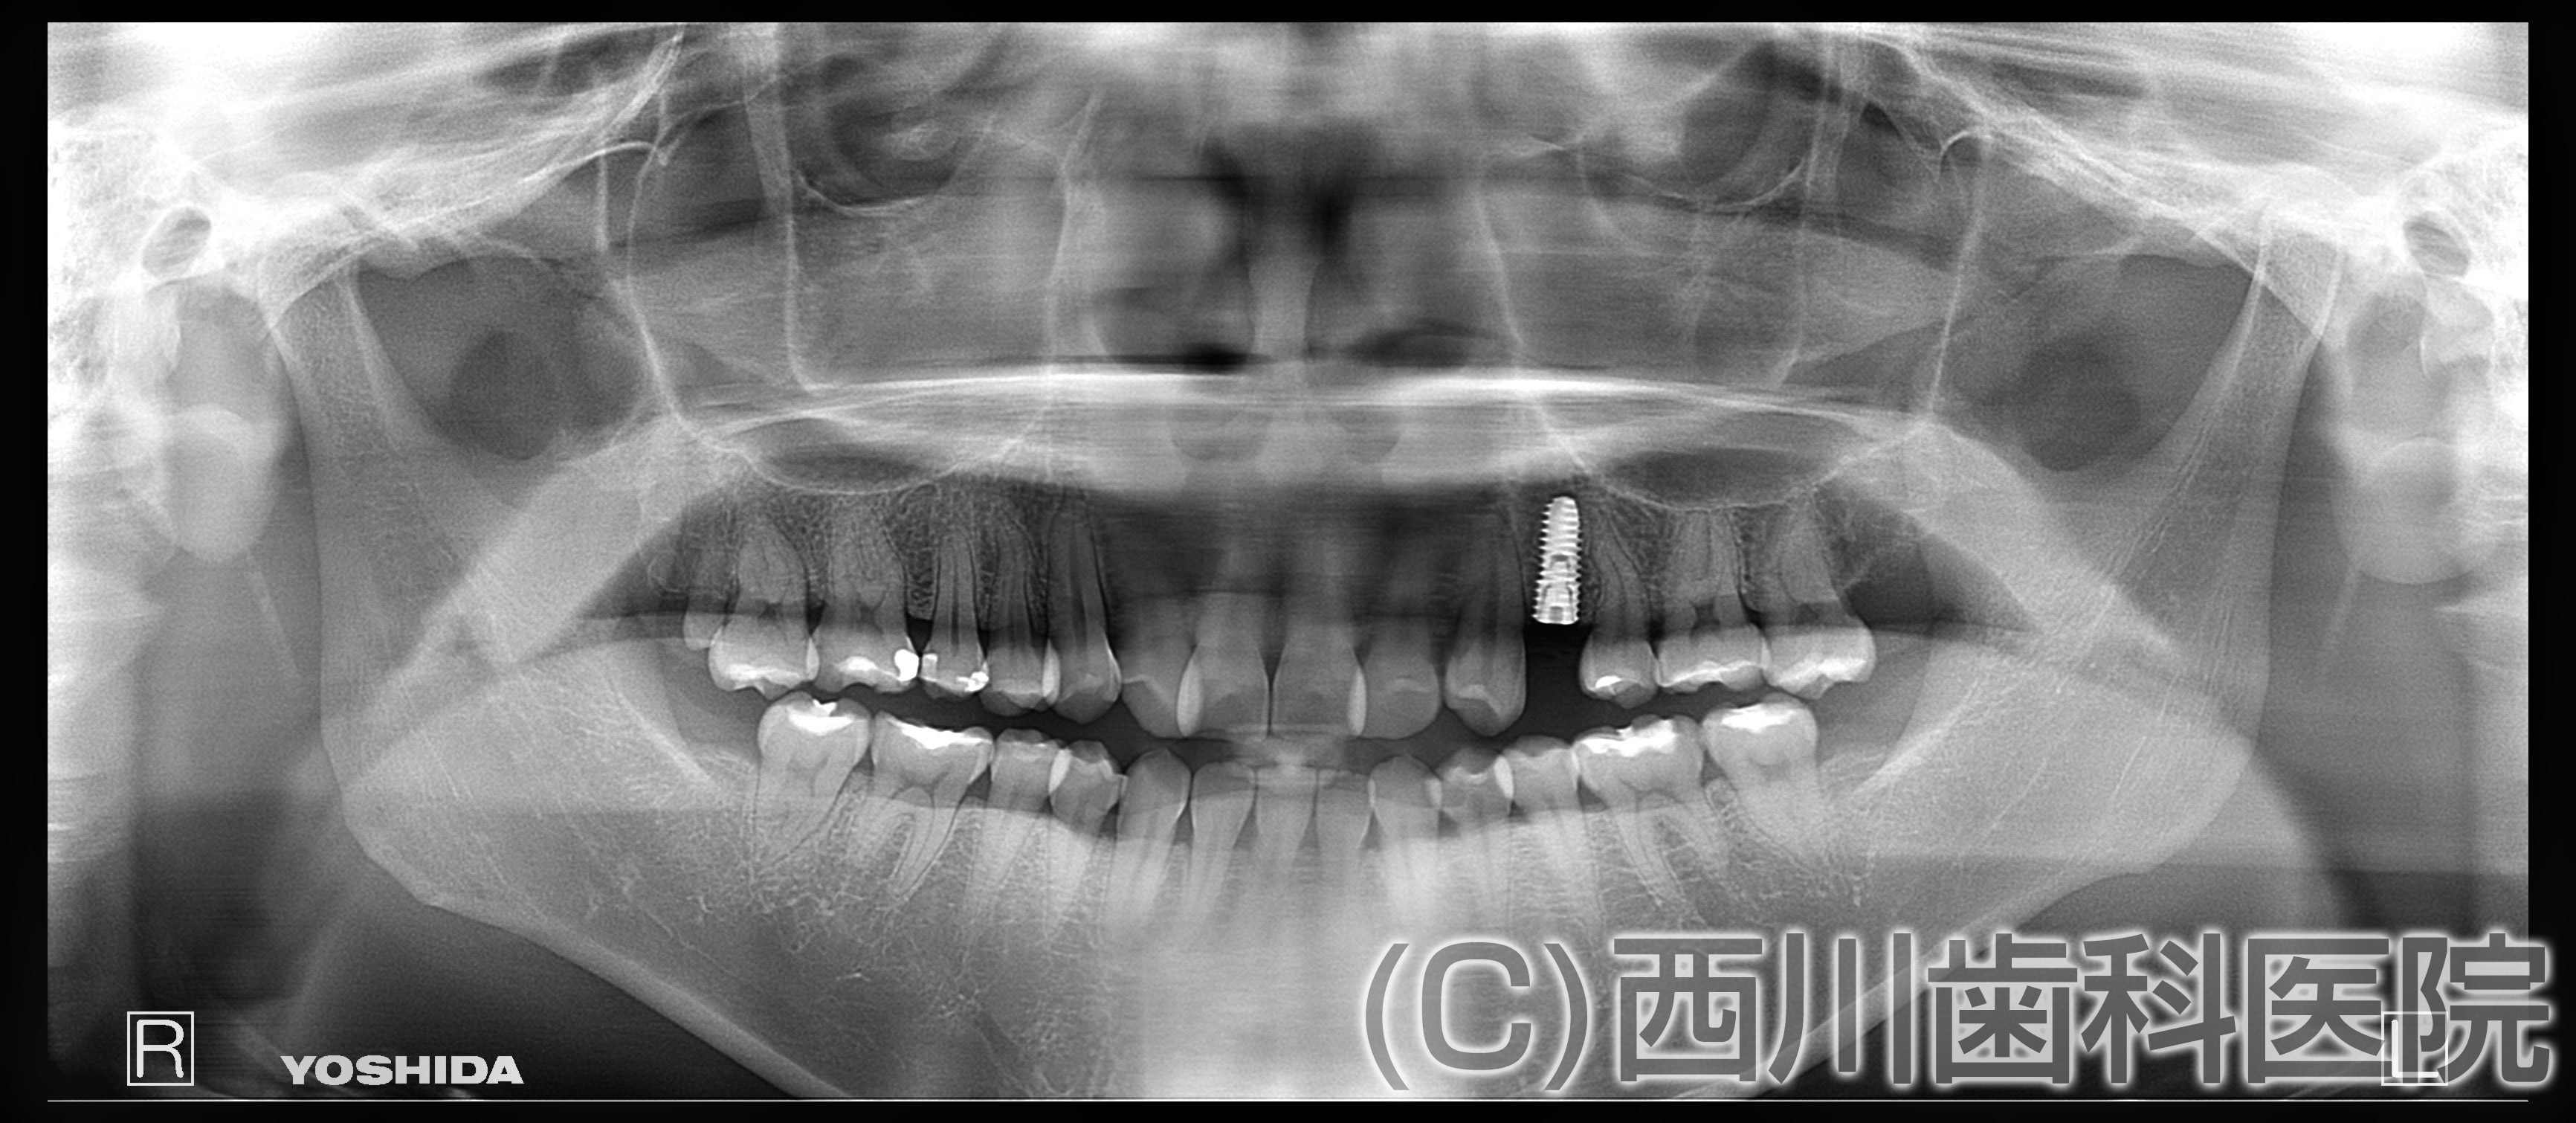

診断 左上4番、歯根破折

初診時の年齢 40歳

治療内容 左上4抜歯、GBR、インプラント埋入

治療期間 11ヵ月

治療費

合計 ¥444,700

治療のメリット:隣り合う健康な歯を削らずにかみ合わせを回復できる。

かみ合わせに非常に重要な犬歯を保存することができる。

リスク:出血、術後の痛み、外科的な処置が必要